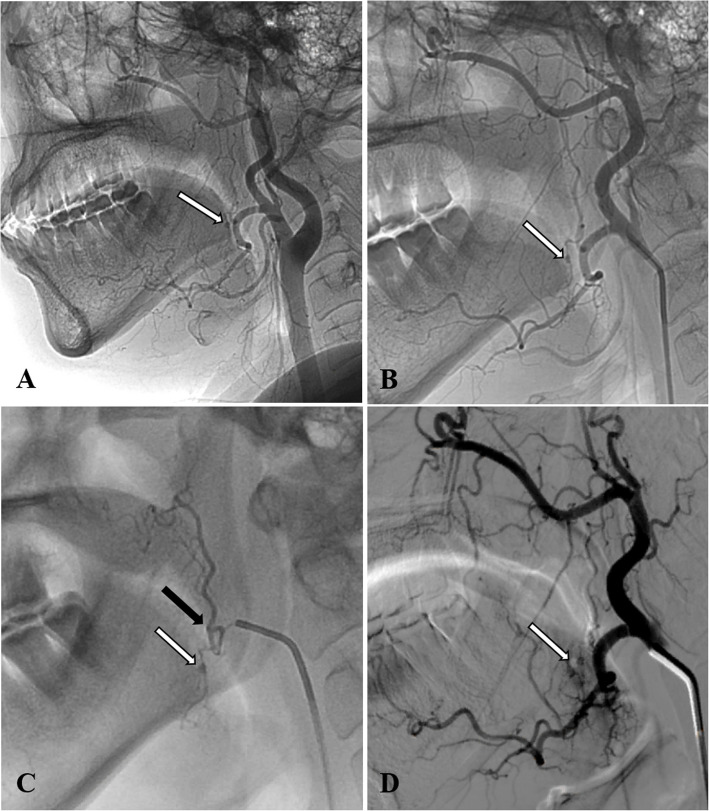

Results: The angiogram revealed pseudoaneurysms in the ascending palatine artery in two patients, the facial artery in one patient, and the lingual artery in the other patient. Two patients were treated with endovascular embolization using n-butyl-2-cyanoacrylate (NBCA) glue, one patient was treated with coils, and one received a combination of coils and NBCA glue for embolization. All procedures were successful, with no clinical complications or rehemorrhage reported.